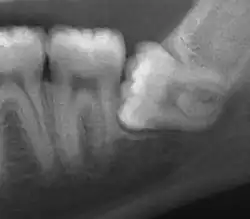

Impacted wisdom tooth with a horizontal orientation

An ectopic tooth, also known as an impacted tooth, is a tooth that develops in an abnormal position (ectopia) and fails to erupt into its normal location in the oral cavity.[1] [2] Ectopic teeth can cause a variety of symptoms, such as pain, swelling, and infection, and they can lead to more serious complications if left untreated.

Ectopic teeth may commonly occur within the dentate region of the jaws. Other common sites for ectopic teeth include the maxillary sinus, the nasal cavity, the mandibular condyle, and the palate.[3] The cause of ectopic teeth is not always clear, but it may be related to genetic factors or developmental abnormalities.[4]

Diagnosis of ectopic teeth typically involves a comprehensive dental examination, including X-rays and other imaging tests. Treatment options for ectopic teeth depend on the location and severity of the condition, as well as the age and overall health of the patient. In some cases, observation and monitoring may be sufficient, while in other cases, surgical intervention may be necessary to remove the ectopic tooth and prevent further complications.[5]